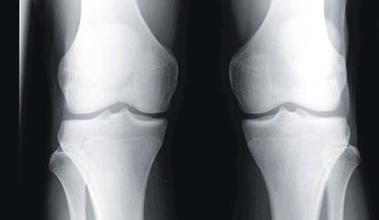

骨刺到底是不是病,治療骨刺的偏方

文章簡介:骨刺到底是不是病,治療骨刺的偏方,大家身邊是不是有一群受骨刺折磨的朋友,親人,同事等??粗麄冇羞@些病痛是不是感覺為他感覺到惋惜?那什么是骨刺?骨刺簡單的說就是骨質(zhì)增生。那治療骨刺的偏方有哪些呢?